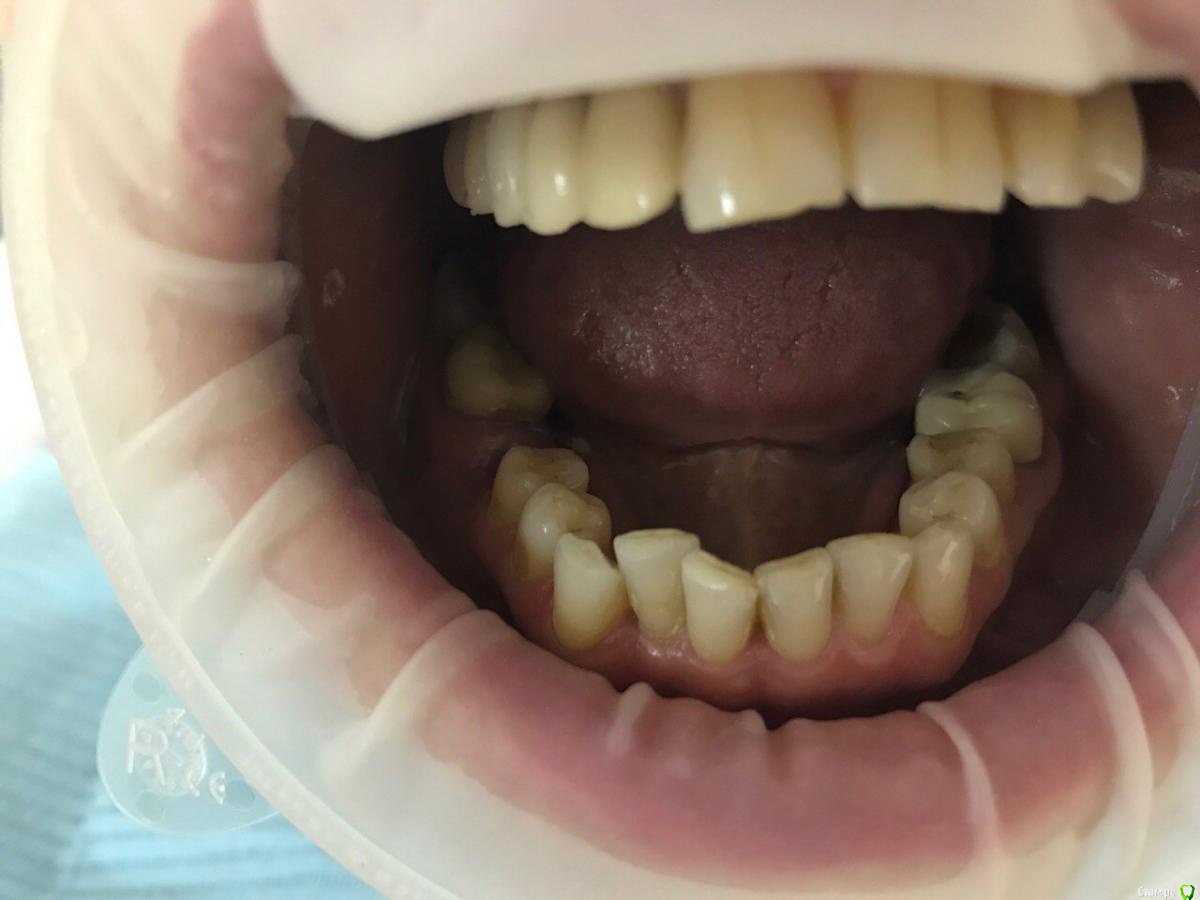

ksenistom Опубликовано 13 декабря, 2016 Поделиться Опубликовано 13 декабря, 2016 Пациентка И.,55 лет,хочет голливуд на обеих челюстях,в виде циркониевых коронок,справа сверху снят мостовидный протез,где установлены 2импл. неделю назад и удалён ретинированный клык в обл 13зуба(фото панорамы нет),поэтому эту сторону пока не трогаем,в области 46 планируется имплантация, 36зуб-вкладка+коронка,в области скученных нижних зубов сделан воксап.Вопрос в том,с чего начать?! Ссылка на комментарий